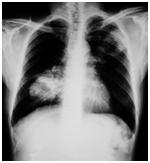

51岁患者陈某因咳血、气喘、行动不便等症状赴港求医,结果检查后发现肺部有两个6公分大的肿瘤,且已扩散到脑部、肝脏和骨骼,病情加重后,行动不便,需要使用轮椅。医生为他进行肿瘤基因测试,结果发现,肿瘤出现EGFR基因突变,更带有exon 19 deletion缺损,因此为他安排接受脑和骨扩散的放射治疗的同时,服用阿法替尼。约一个月后,他的病情明显受到控制,可以不再用轮椅,第二个月后,主要的肺内肿瘤明显缩小,脑部肿瘤消失,而肝脏肿瘤则缩小至只有一公分。他至今仍然服用阿法替尼,体重正常,享有接近无肿瘤征状的高生活质量。